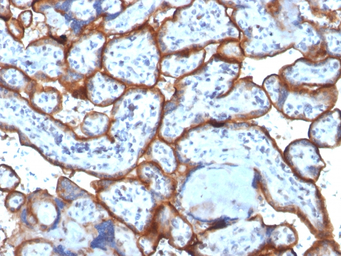

IHC-P analysis of human bone marrow tissue using GTX34550 CD71 antibody [TFRC/1818].

IHC-P analysis of human placenta tissue using GTX34550 CD71 antibody [TFRC/1818].